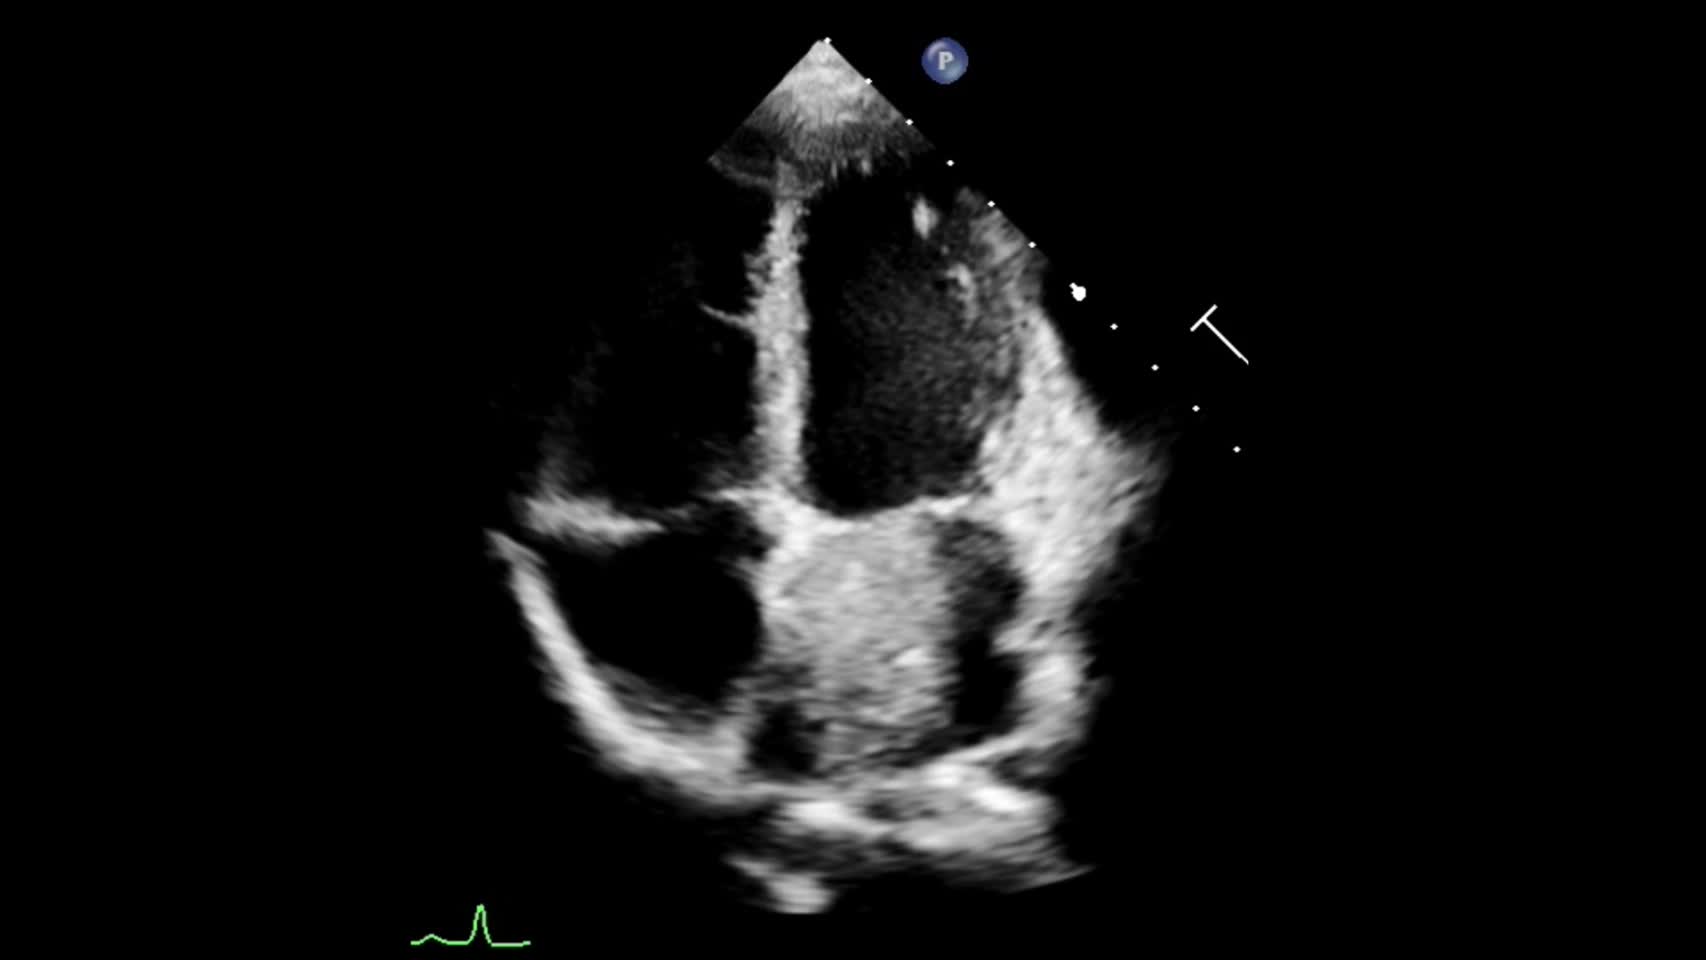

動画20-2 心エコー②(心尖部四腔像)...

00:00:02